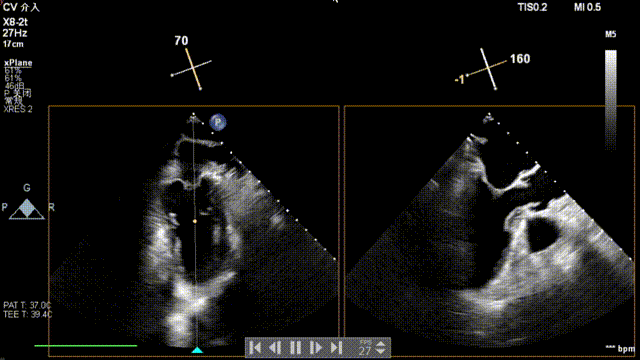

术前超声

患者为原发性二尖瓣反流(DMR),收缩期可见二尖瓣反流信号,反流位于 2 偏 3 区,基线期二尖瓣反流程度4+。

前叶长度 15.7mm,后叶长度 12.7mm,后叶脱垂宽度13.9mm,脱垂高度4.76mm, 瓣环直径37.1mm,VC:4*7mm, MVA约4cm² 。瓣叶质地较差,腱索断裂、后瓣叶脱垂。